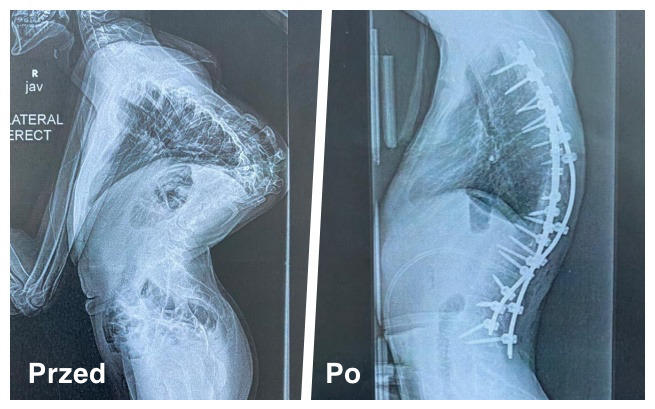

Teraz kręgosłup Aleksa utrzymują 3 druty i 22 śruby. Kontynuujemy rehabilitację w domu zgodnie z otrzymanym programem ćwiczeń.

Pierwszy etap operacji został przeprowadzony planowo 15 czerwca. Operacja polegała na poluźnieniu kręgów kręgosłupa i wykonaniu osteotomii. Lekarze zadecydowali, że wyciąg zostaje, by rozciągnąć kręgosłup do tego stopnia, gdy możliwe będzie założenie trwałego usztywnienia. Jest już bardzo widoczny efekt po tej operacji!

Po lewej: przed operacjami i po pierwszym etapie leczenia.

Po lewej: kręgosłup Alka przed operacjami w USA.